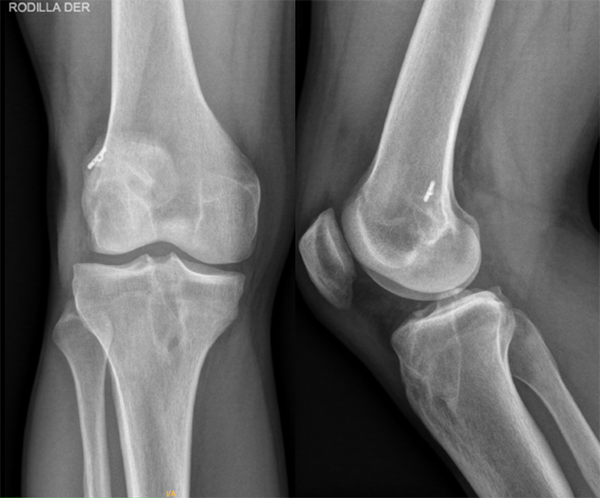

Al examen físico se evidenciaba rodilla derecha con recurvatum (paciente hiperlaxo), tumefacta, con moderado derrame articular y presencia de choque patelofemoral, limitación del rango de movilidad por dolor, maniobras de Lachman (+++/+++) y Pivot shift (+++/+++, explosivo), signos meniscales internos y externos, translación y rotación interna tibial. Se solicitó un par radiográfico de esa rodilla, en la que se evidenciaron túneles femorales y tibiales realizados con técnica anatómica (transportal medial) con satisfactoria ubicación y orientación, sin aumento de tamaño significativo (diámetro y longitud) (fig. 1). Se evaluó específicamente la pendiente o slope tibial, sin encontrarla aumentada. Debido a esto no se consideró necesario complementar estudios de imágenes preoperatorios con tomografía computada (TAC).

Figura 1: Rx rodilla derecha frente y perfil.